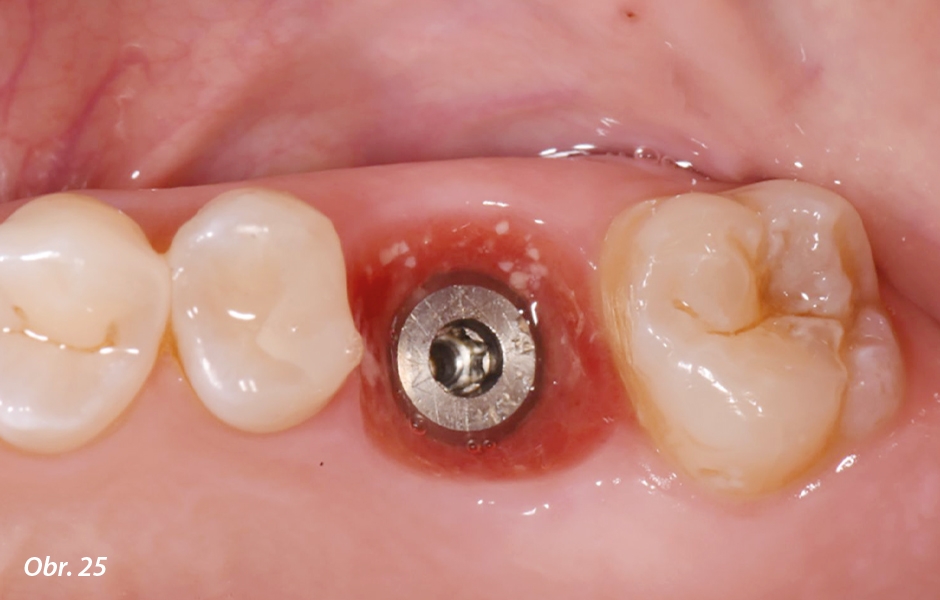

Po dvou měsících bezproblémového hojení se pacientka vrátila na závěrečné digitální otiskování intraorálním skenerem (Virtuo Vivo™; Institut Straumann AG). Na implantát bylo točivým momentem 15 Ncm připevněno skenovací tělísko (CARES® Mono Scanbody; Institut Straumann AG). Intraorální skeny a virtuální záznam skusu byly exportovány ve formátu polygonového souboru (PLY) a importovány do CAD/CAM softwaru (CARES® Visual; Institut Straumann AG) za účelem navržení definitivní náhrady na prefabrikovaném abutmentu (Variobase® Crown; Institut Straumann AG). Definitivní korunka byla vyfrézována z vícevrstvého vysoce translucentního zirkonu (zerion® UTML; Institut Straumann AG). Na definitivní zirkonovou korunku byly doplněny povrchové individualizace a nanesena glazura. Korunka byla pomocí pryskyřičného cementu připevněna na prefabrikovaný abutment. Po intraorální kontrole estetických a funkčních aspektů byla definitivní korunka připevněna na implantát momentem 35 Ncm. K zapečetění přístupu ke šroubu byl použit teflon a světlem polymerující kompozit (obr. 25–30).